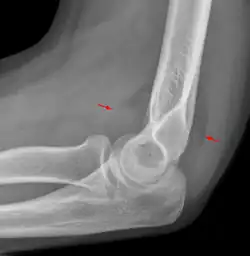

Fat pad sign

The fat pad sign, also known as the sail sign, is a potential finding on elbow radiography which suggests a fracture of one or more bones at the elbow. It may indicate an occult fracture that is not directly visible. Its name derives from the fact that it has the shape of a spinnaker (sail).[1] It is caused by displacement of the fat pad around the elbow joint. Both anterior and posterior fat pad signs exist, and both can be found on the same X-ray.

In children, a posterior fat pad sign suggests a condylar fracture of the humerus. In adults it suggests a radial head fracture.

The fat pad sign is invaluable in assessing for the presence of an intra-articular fracture of the elbow. An anterior fat pad is often normal. However a posterior fat pad seen on a lateral x-ray of the elbow is always abnormal. The patient will be unable to flex their elbow and requires orthopaedic input.[2]

The posterior fat pad is normally pressed in the olecranon fossa by the triceps tendon, and hence invisible on lateral radiograph of the elbow.[3] When there is a fracture of the distal humerus, or other pathology involving the elbow joint, inflammation develops around the synovial membrane forcing the fat pad out of its normal physiologic resting place. This is visible as the "posterior fat pad sign" and is often the only visible marker of a fracture, particularly in the pediatrics population.